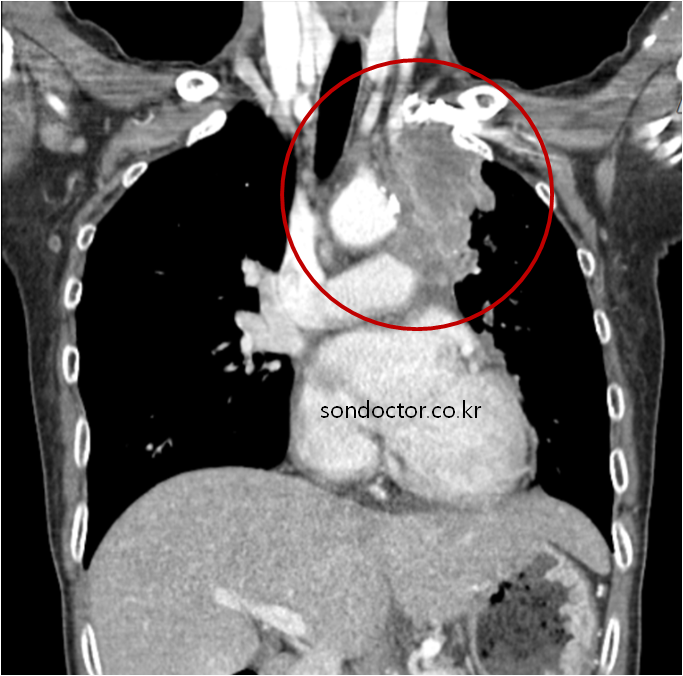

아래 붉은 원안에 뭔가 종괴같은 음영이 보입니다. 크기도 굉장히 크고 대동맥 같은 중요 혈관 주변에 위치하고 있습니다. 호흡을 하여 공기가 지나다니는 기관과 기관지를 밀어내는 종괴같습니다. 크기나 모양, 주변 장기를 밀어내는 모양새가 심상치 않습니다. 왠지 왼쪽 어깨가 계속 아팠던 원인도 이 종괴 때문이지 않을까 싶습니다. 종괴 근처의 신경을 압박했기 때문일 것입니다.

CT 를 촬영하였고 역시 9~10cm 되는 크기의 폐암이 의심되는 판독이 나왔습니다. 종양의 크기도 컸지만, 반대쪽 폐에도 전이로 의심되는 종괴가 있다는 점이 아쉬웠습니다. 즉 암세포가 반대쪽 폐까지 넘어가서 자라고 있다는 뜻이므로, 다른 먼 장기에도 전이되었을 가능성이 큽니다.